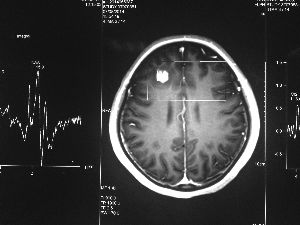

方框亮點(diǎn)為CT片顯示的異物

今年6月份,張敏在宿舍休息時(shí),又發(fā)起了癲癇,也是口吐白沫,渾身抽搐。送到蘇州一家大醫(yī)院,頭顱核磁共振檢查出,張敏大腦右額葉處有一處病灶,也就是大腦額頭處有個(gè)東西。

腦袋里的東西,到底是腫瘤還是其他什么東西,這個(gè)謎像個(gè)石頭一樣,壓得張敏一家人喘不過氣。7月份,張敏一家又來到南京腦科醫(yī)院求醫(yī),第三次檢查后,醫(yī)生覺得很像是寄生蟲。不過,影像的檢查,只能作為醫(yī)生推測的依據(jù),具體是什么,只有手術(shù)拿出來后才能知道。